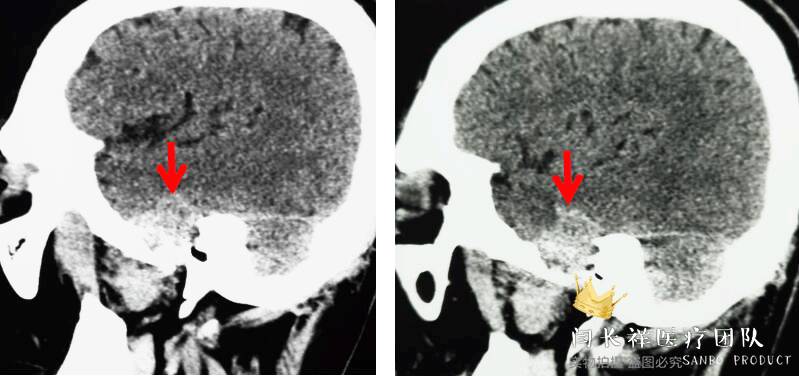

中颅窝-颞下窝占位

术前矢状位CT。

术前冠位CT骨窗像示右侧中颅窝底骨质被肿瘤侵蚀破坏。